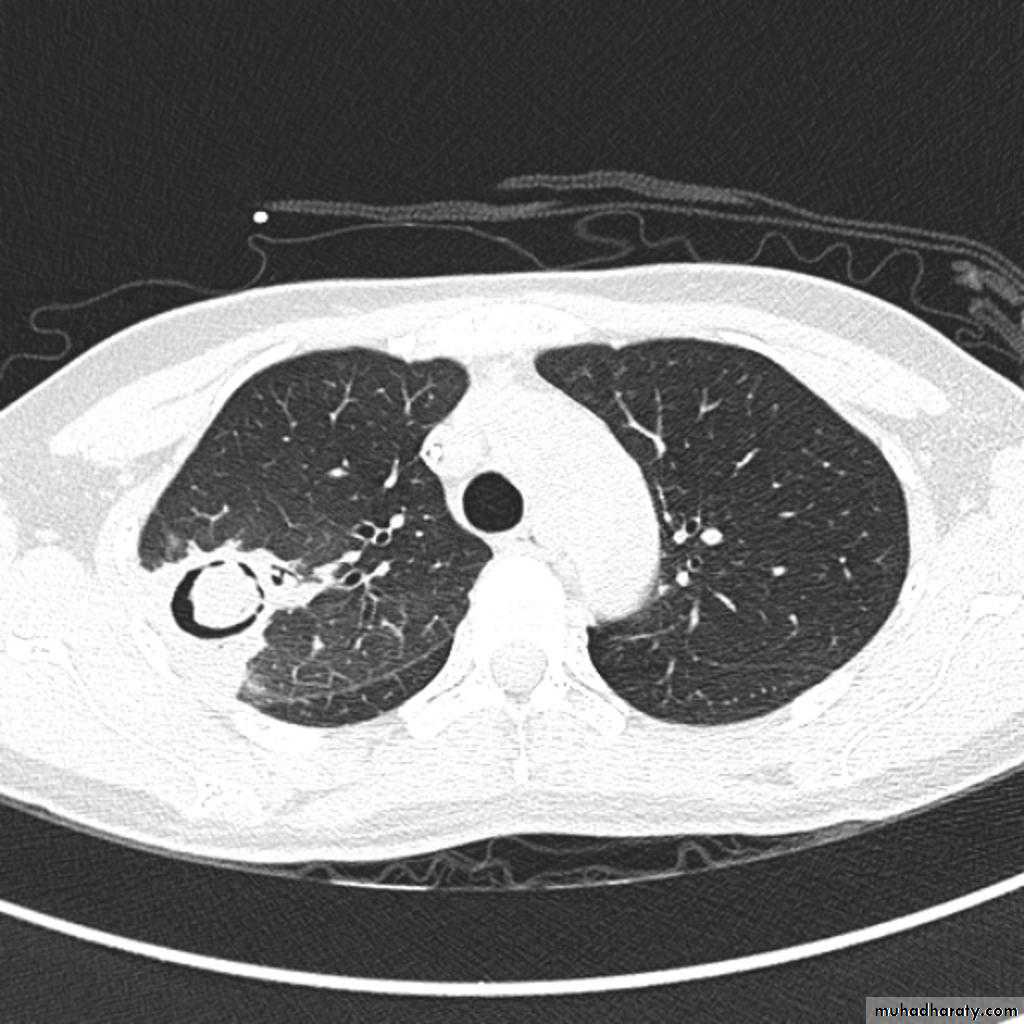

TB abscess

1.patchy consolidation or poorly defined linear and nodular opacities in both apices , upper zone in one lung , & lower zone in other lung ( ulternating lesion ) .2. Post-primary infections are far more likely to cavitate with multiple abscess formation & air fluid level more develop in the posterior segments of the upper lobes.

Recognized complications include:1.colonisation of cavities by fungus, e.g. aspergilloma

Aspergiloma